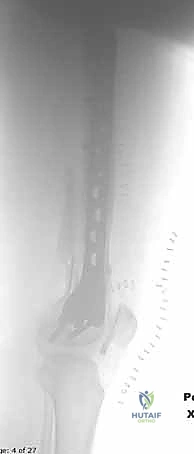

المرحلة الثانية: الفتح الجراحي والوصول للعظم

يستخدم الدكتور هطيف تقنيات الفتح الجراحي المحدود (Minimally Invasive Plate Osteosynthesis - MIPO) كلما أمكن ذلك، للحفاظ على التروية الدموية للعظم وتسريع الالتئام. يتم عمل شق جانبي بعناية للوصول إلى منطقة الكسر دون الإضرار بالعضلات المحيطة.

المرحلة الرابعة: التثبيت النهائي بالشرائح والمسامير (Fixation)

يتم استخدام "شرائح الإغلاق التشريحية" (Anatomical Locking Plates) المصنوعة من التيتانيوم عالي الجودة. هذه الشرائح مصممة خصيصاً لتأخذ شكل الجزء السفلي من عظم الفخذ. يتم تمرير الشريحة أسفل العضلات وتثبيتها بمسامير تغلق داخل الشريحة نفسها (Locking Screws)، مما يوفر ثباتاً ميكانيكياً هائلاً، حتى في حالات العظام الهشة.